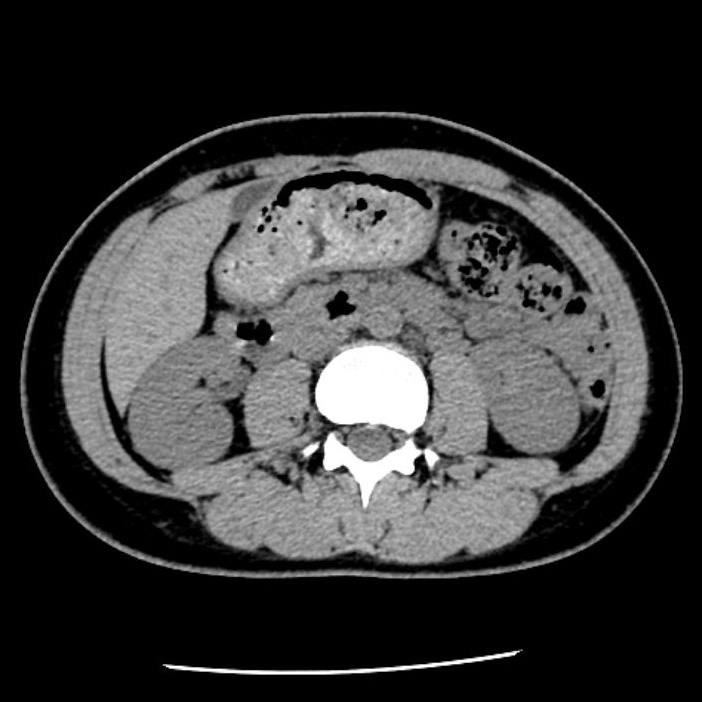

CT室:Aquilion ONE (Canon)・Revolution EVO (GE)

CTとは、X線という放射線を使用して人体の輪切り画像を撮る装置です。その画像を使用して、さまざまな方向の断面像や3Dの画像を再構成をすることもあります。

当院には320列と64列のCTがあります。

■64列CT (Revolution Evo)

心臓以外の検査全般